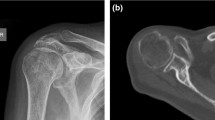

Radiological evaluation of rotator cuff tendon damage and glenohumeral arthritis was performed based on the available conventional X-rays, CT and MRI scans (Figs. 1a–d, 2a–c). Table 1 shows the results of radiological assessment of orthopaedic and trauma shoulders (4-part or Neer Type VI dislocated proximal humerus fractures).

According to the Walch classification, grade ‘D’ in the case of sample B2 indicates a very severe arthritis with anterior humeral head subluxation and level ‘A1’ in the case of sample A3 means a well-centred humeral head with only minor erosions. Based on MRI scans, Outerbridge ‘grade 2’ of sample B1 means blister-like swelling/fraying of articular cartilage extending to surface, a moderately damaged cartilage. The Hamada classification indicates the progression of rotator cuff tear arthropathies (from 1 to 5). Of the trauma samples, A3 was graded as ‘4b’ and orthopaedic samples B1 and B2 were graded as ‘4A’ and ‘5’, respectively, demonstrating a worse prognosis of arthropathy for the orthopaedic patients.